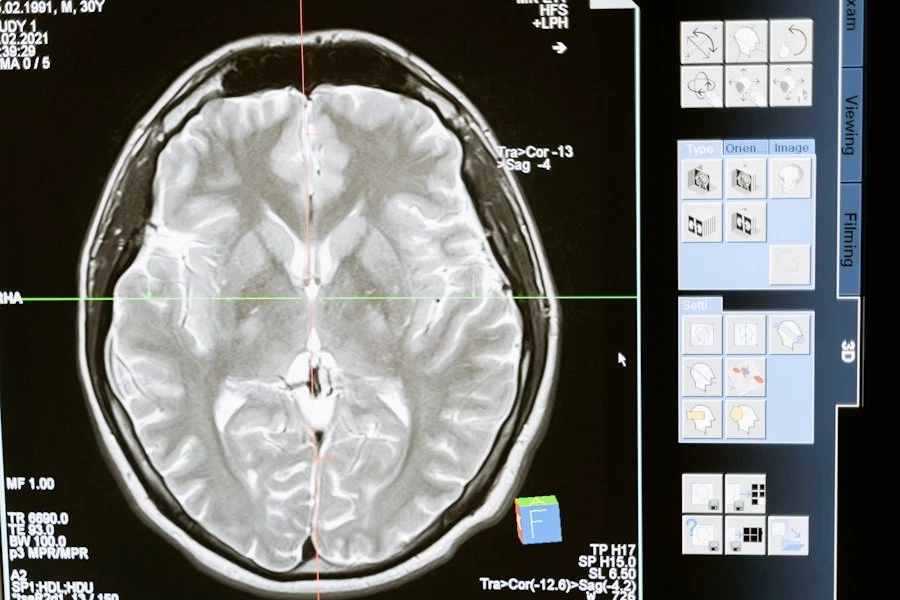

Исследователи из Университета Майами сделали важное открытие: проблемы с дыханием во время сна, такие как апноэ и гипопноэ, могут вызывать изменения в структуре мозга. Это открытие проливает свет на сложную связь между качеством сна, памятью и старением мозга. Работа опубликована в журнале Neurology.

В исследовании приняли участие 2 667 человек со средним возрастом 68 лет, преимущественно латиноамериканского происхождения. В рамках эксперимента они прошли домашнее тестирование сна, позволяющее зафиксировать остановки дыхания и замедления. На основе этих данных участников разделили на три группы: без нарушений дыхания, с лёгкими нарушениями и с тяжёлыми нарушениями. Через 10 лет все добровольцы прошли сканирование мозга.

Результаты анализа показали, что у людей с тяжёлыми нарушениями дыхания объём гиппокампа — области мозга, ответственной за память и мышление, — оказался на 0,24 кубического сантиметра больше, чем у тех, кто спал без проблем. Более того, каждое дополнительное нарушение дыхания приводило к увеличению объёма гиппокампа на 0,006 кубического сантиметра.

Ещё одна важная находка связана с уровнем кислорода в крови. Учёные выяснили, что снижение кислорода во время сна связано с увеличением гиппокампа и повреждением белого вещества мозга. Повреждённые области белого вещества, согласно исследованию, могут нарушать взаимодействие между различными участками мозга.